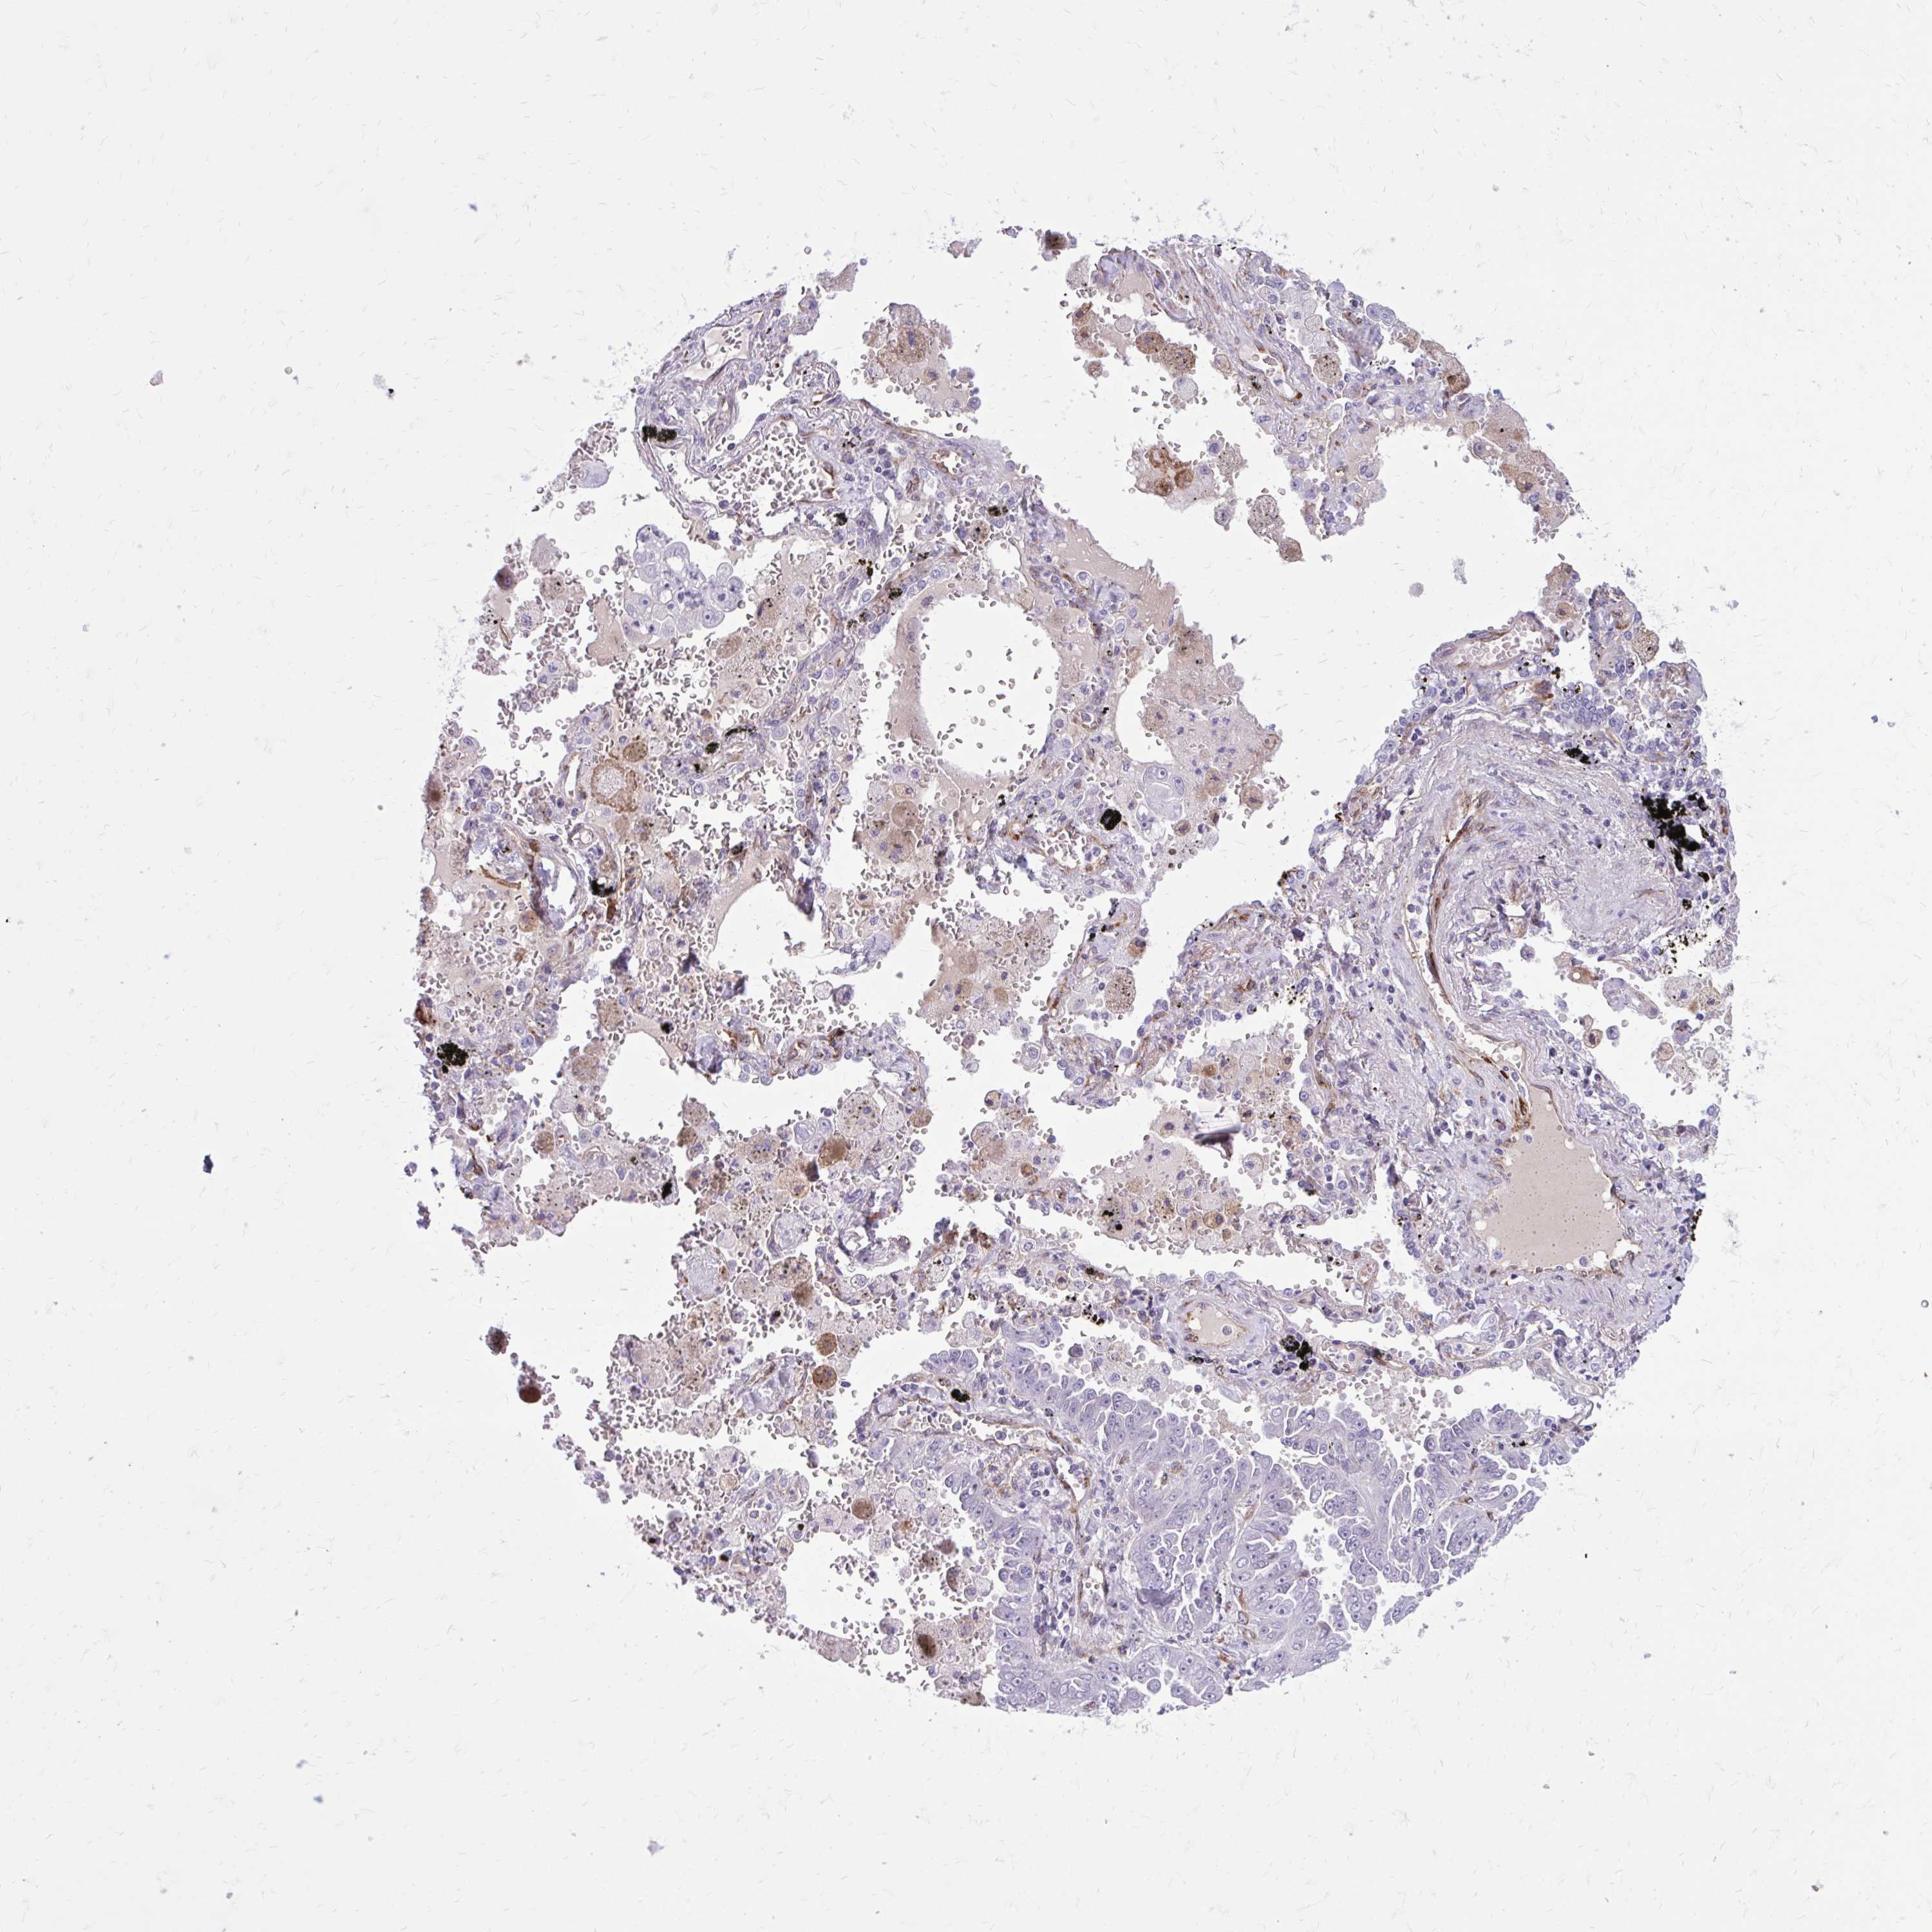

CANCER LUNG CANCER Show tissue menu

BEND5 is not prognostic in Lung Adenocarcinoma (TCGA)